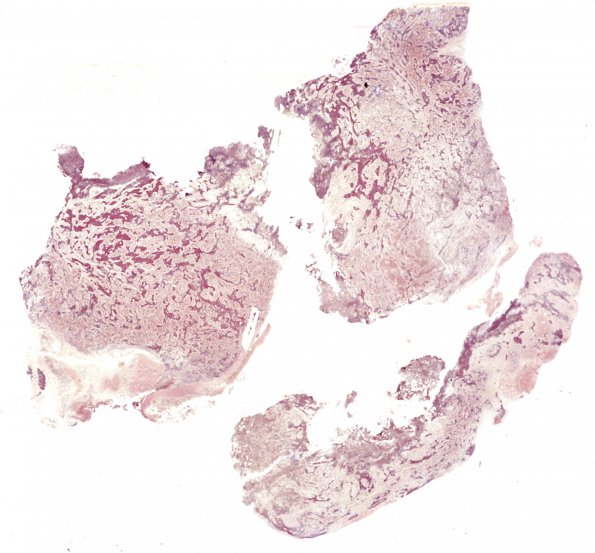

Washington University Experience | NEOPLASMS (EMBRYONAL) | Medulloblastoma, Histologically Defined | Extensive Nodularity (MBEN) | 1F1 Medulloblastoma, nodular (Case 1) 1 Retic 1

1F1-3 Reticulin stain is rich in the internodal phase and not present within the pale islands.